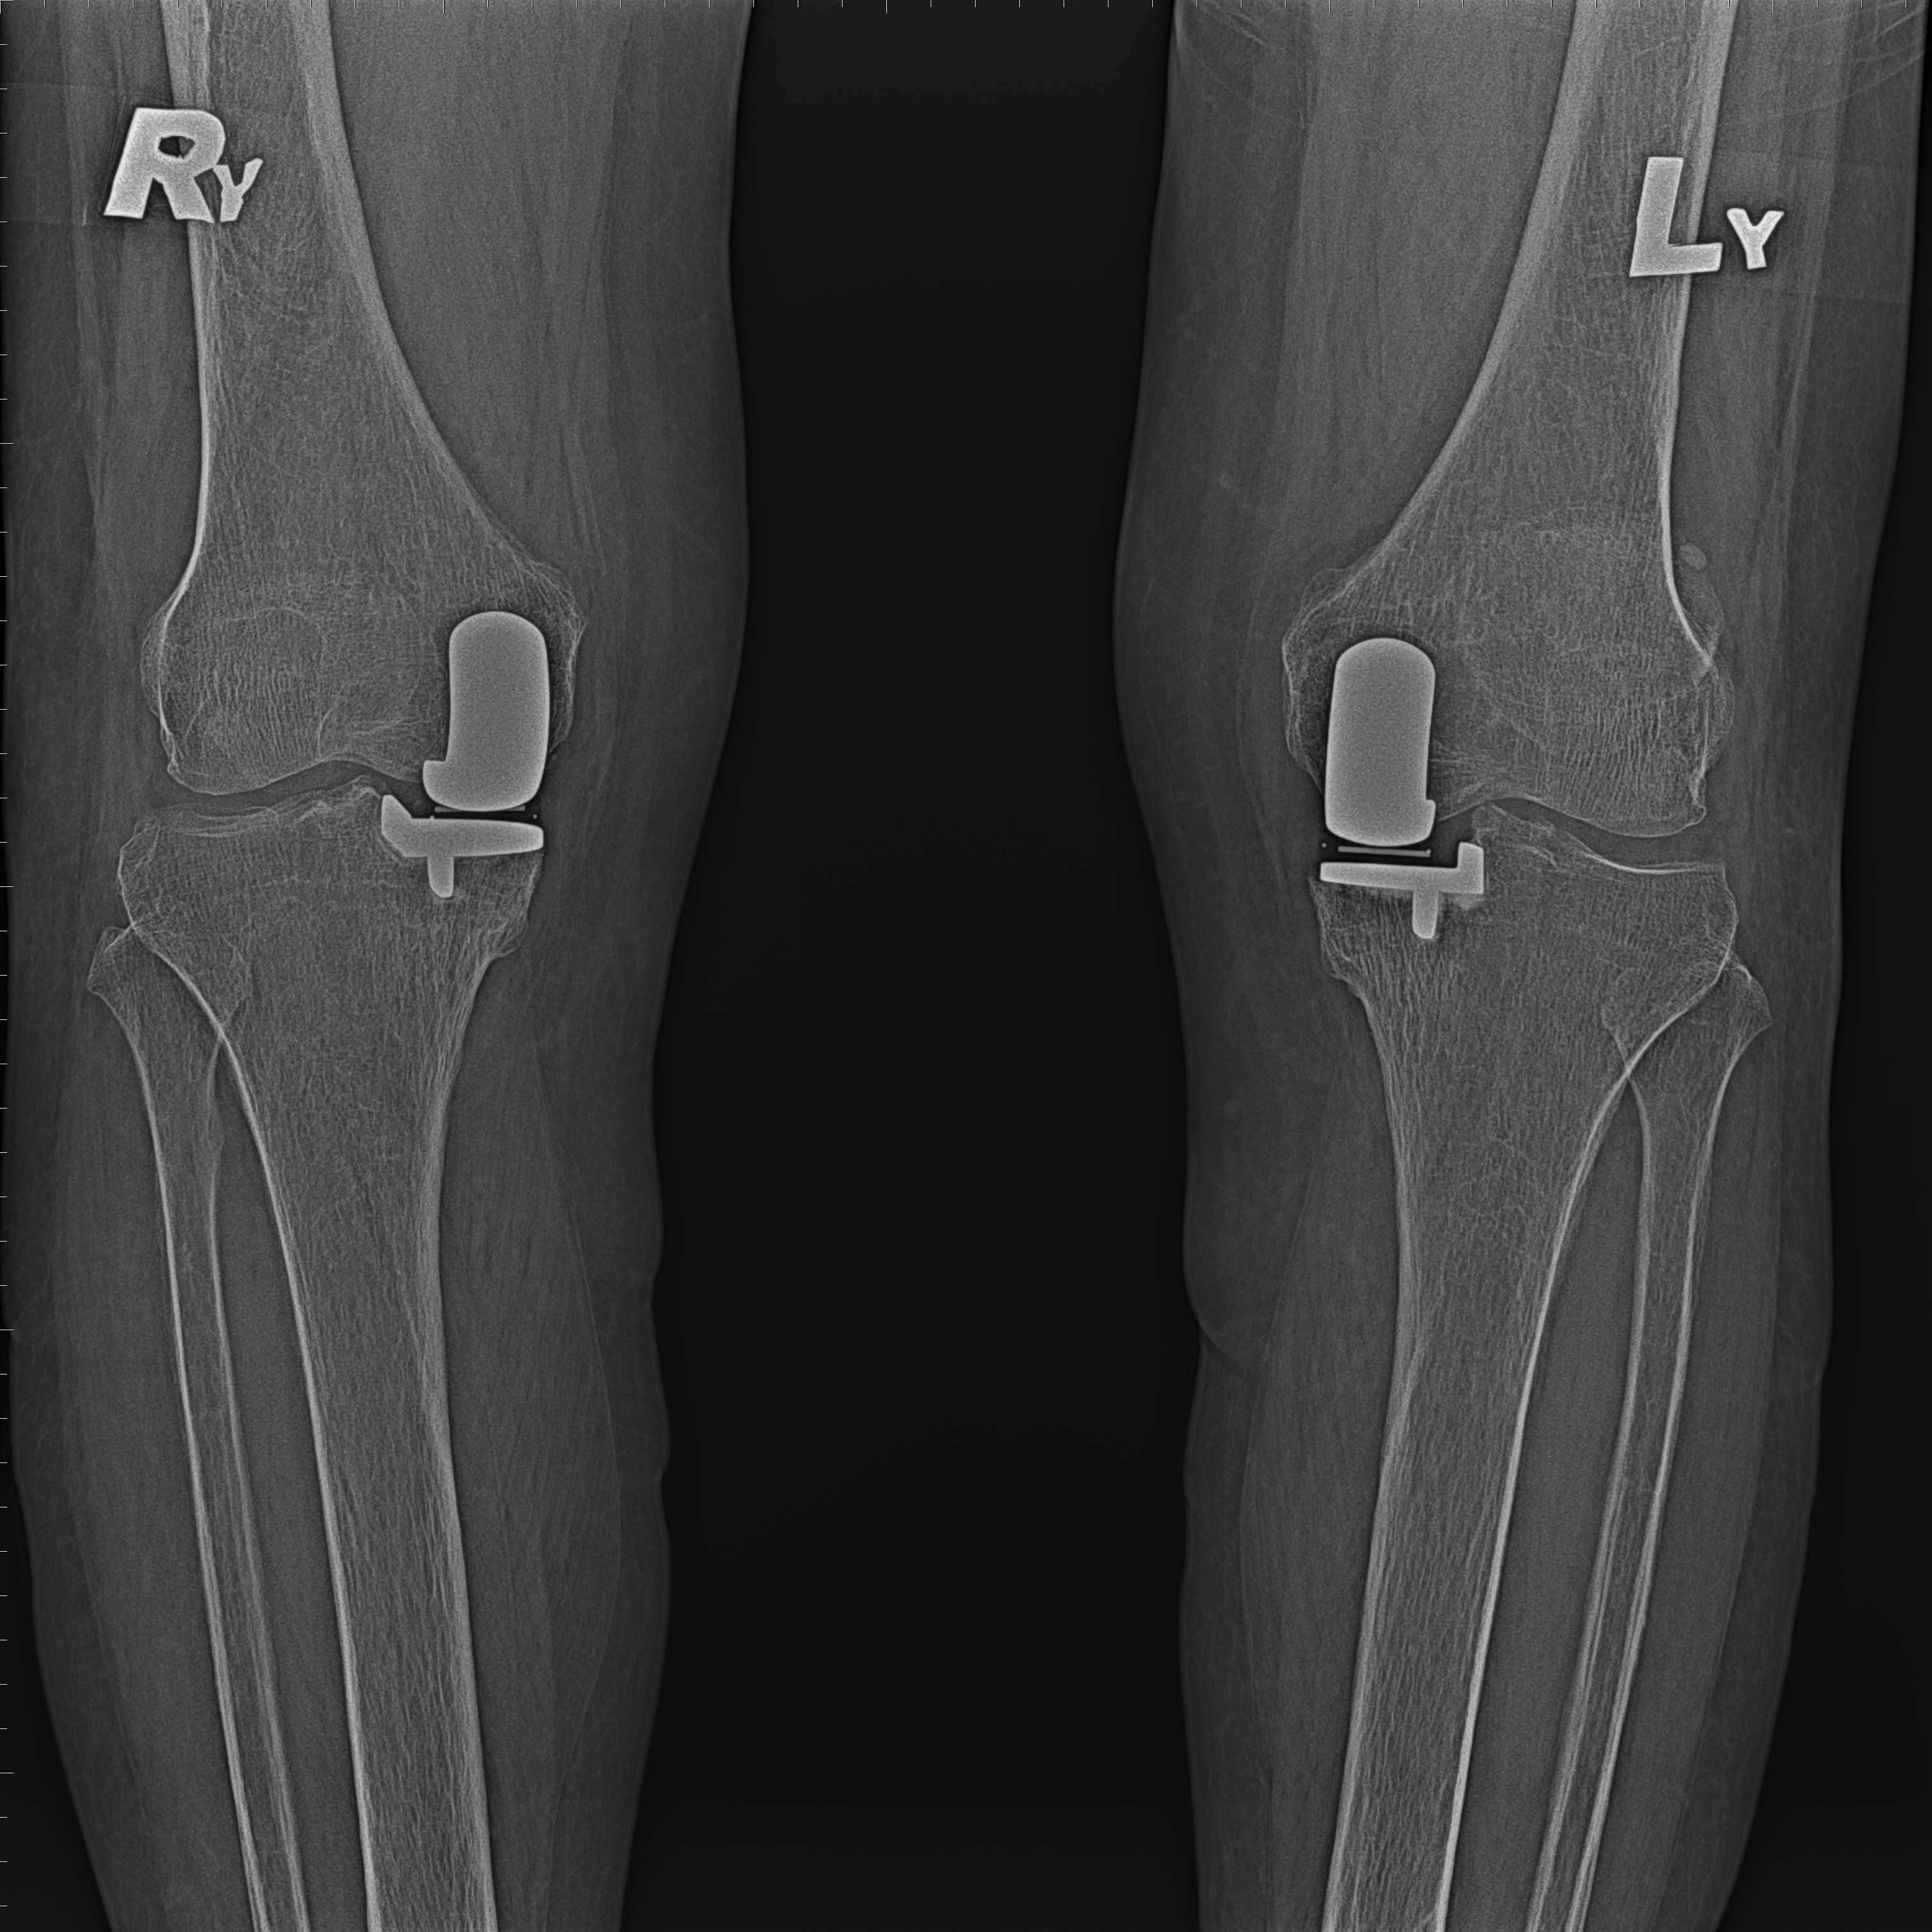

傳統部分膝置換 首頁 案例分享 膝關節手術 傳統部分膝置換 殷女士 65歲 術前 術後 張女士 71歲 術前 術後 蔡女士 74歲 術前 術後 張女士71歲 術前 術後 翁女士70歲 術前 術後 劉女士 80歲 術前 術後